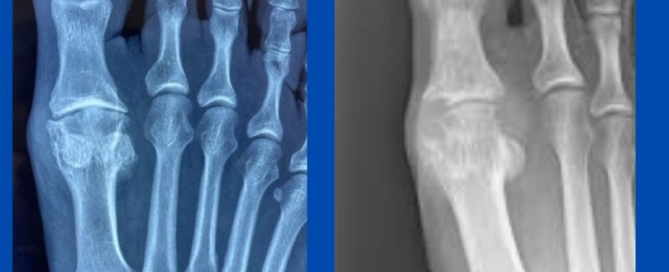

Heloma Molle (interdigital corn)

Blog's main page These things can be so painful! One of my favourite procedures to carry out is the excision of the interdigital corn. As surgery goes, they are quite [...]